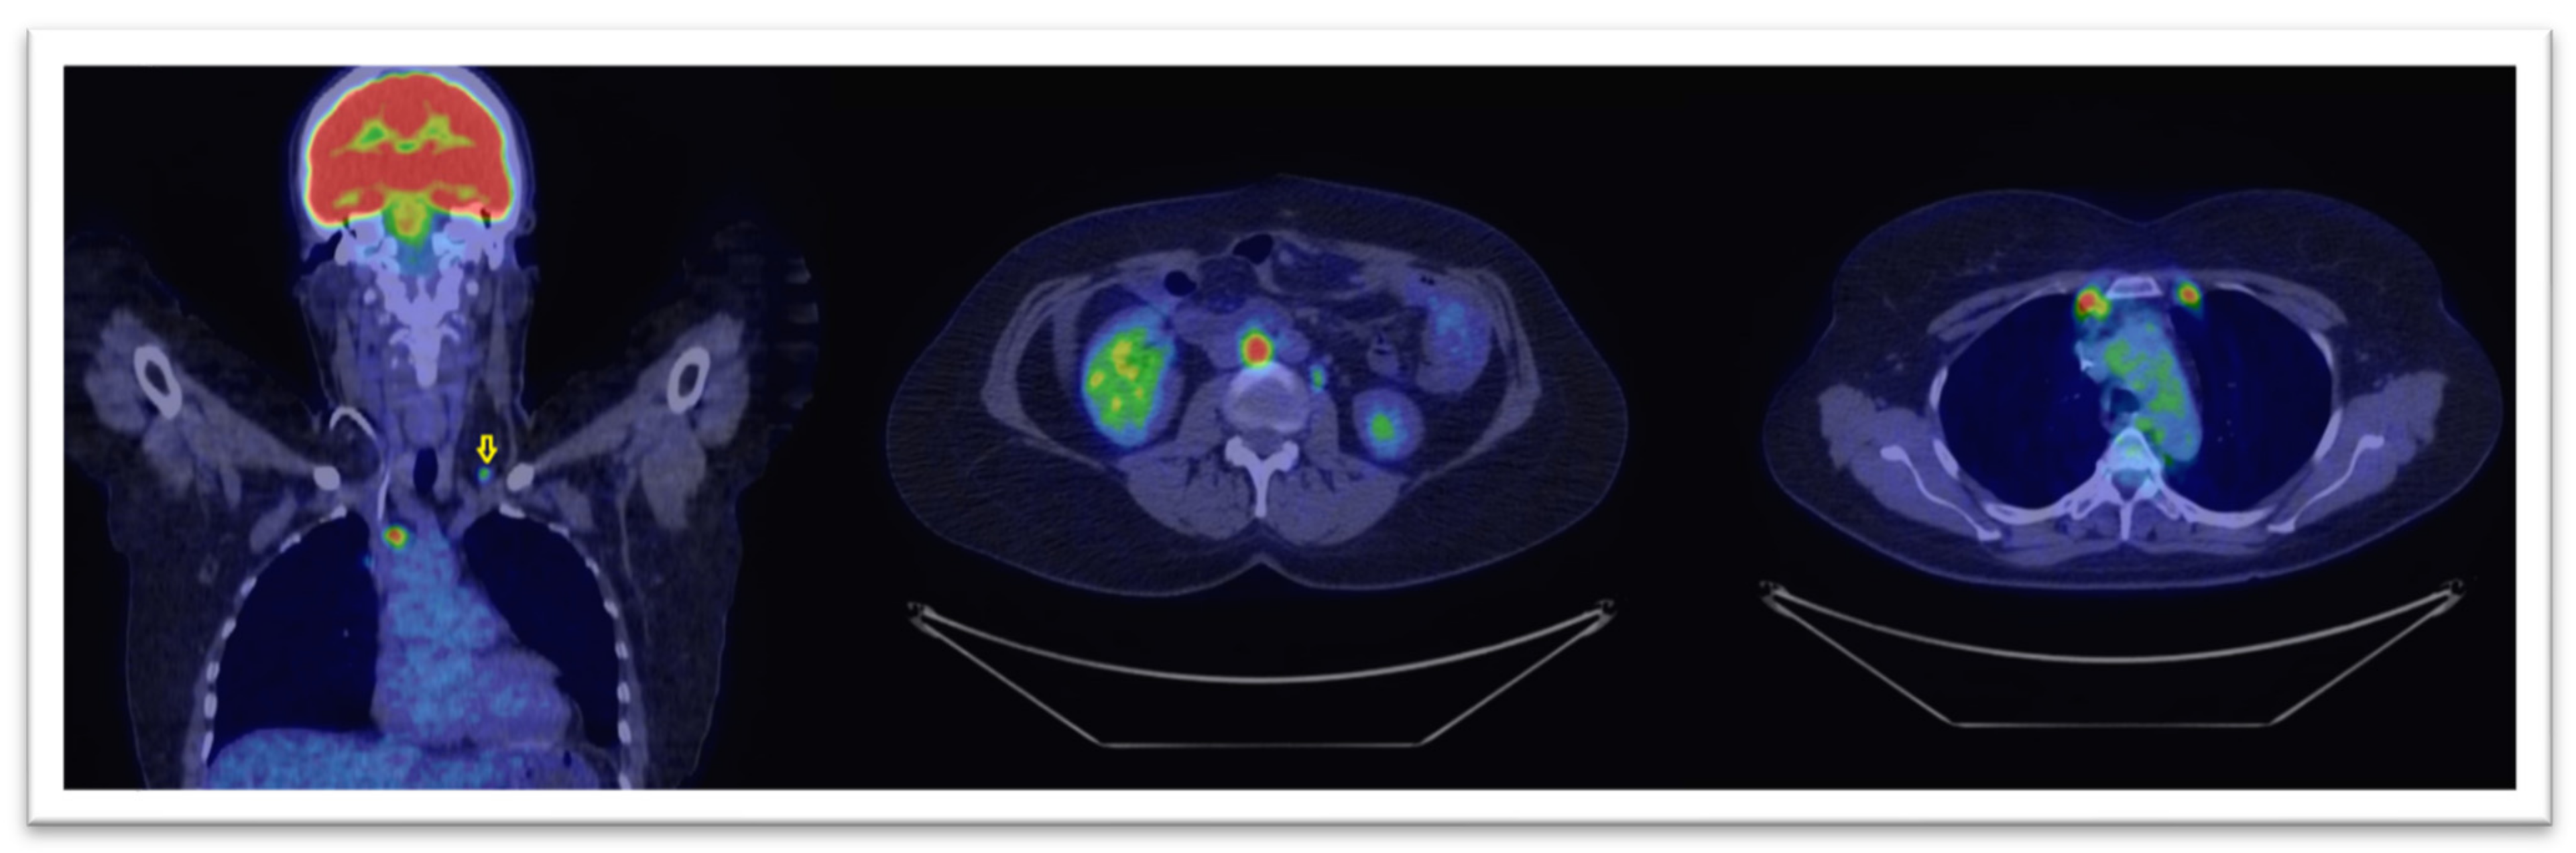

In Figure 4 and Figure 5 we display two cases where, based on PET/CT scans, the therapies had major changings. The modified treatment strategies occurred in our group, are presented in Table 3.

Figure 4.

18F-FDG PET-CT scan with coronal (left image) and axial views (central and right) reveal intense tracer uptake in lumbo-aortic and mediastinal lymph nodes and also in a left supraclavicular one (marked with yellow arrow), in a patient with a CA-125 level of 280 U/mL. The lymphatic spread was suggestive for unexpected progressive disease.